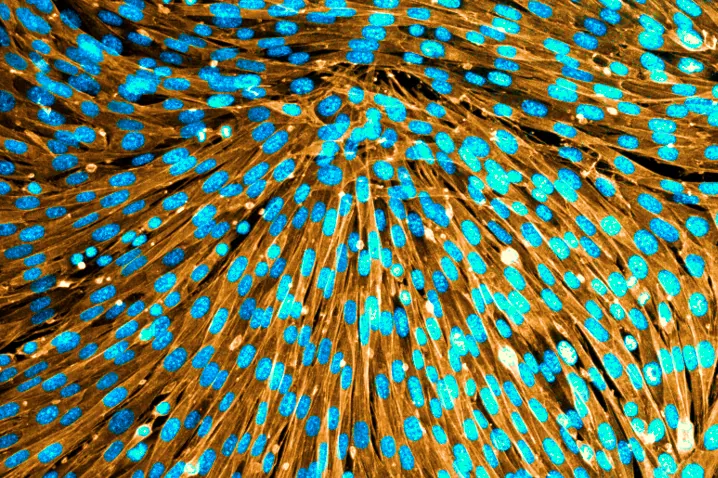

Investigadores españoles han desarrollado una nueva estrategia para lograr dirigir las fuerzas mecánicas de las células y que adopten la forma tridimensional que ellos quieran. El trabajo, publicado en 'Science', abre la puerta a nuevas aplicaciones en medicina regenerativa y robótica biohíbrida...